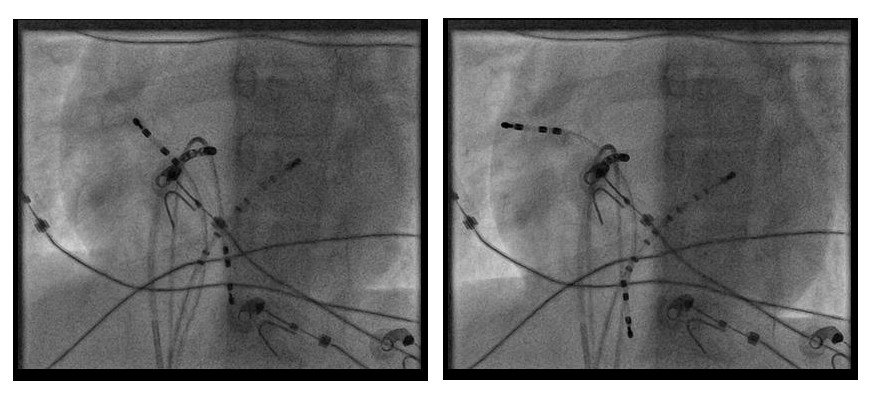

Mapping

09_ablation site.jpg

Pathway potential

08_ablation_signal.JPG